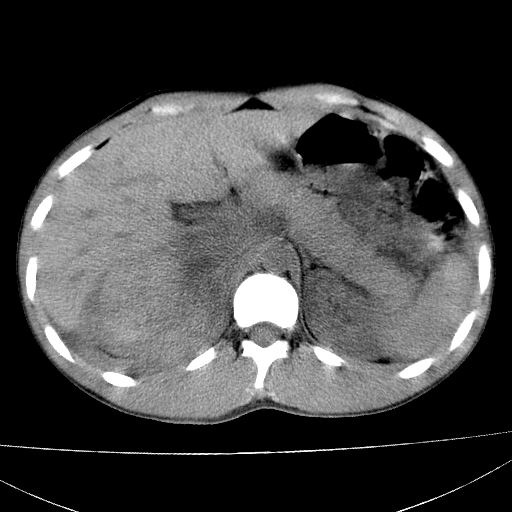

标题: CT15860:男,21岁,腹部外伤2小时伴胸疼。 [打印本页]

标题: CT15860:男,21岁,腹部外伤2小时伴胸疼。

b超示:肝破裂。

肝脏及肾脏明显有损伤性改变并激发腹腔内积液(血),以肝脏撕裂及肾周积血显著。

1)肝破裂伴腹腔积液(血)。2)右肾破裂伴右肾包膜下及肾周血肿。3)腹部空腔脏器穿孔可能。4)右侧少量胸腔积液(血)。